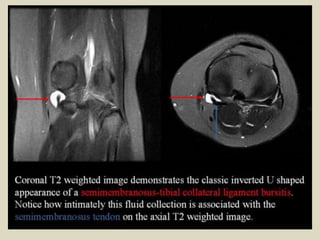

Medial Collateral Ligament Bursitis

The medial collateral ligament bursa is located between the superficial and deep layers of the

medial collateral ligament. Clinically, fluid collection in this bursa mimics a medial meniscus tear

and/or medial collateral ligament tear. On MRI, medial collateral ligament bursitis appears as a

T2 hyperintensity between the superficial and deep fibers of the medial collateral ligament. It

must be differentiated from meniscocapsular separation. In meniscocapsular separation, in

addition to fluid collection between the superficial and deep fibers of the medial collateral

ligament, there is a tear of the peripheral corner of the medial meniscus and meniscal

displacement from the outer cortical margin of the tibia.